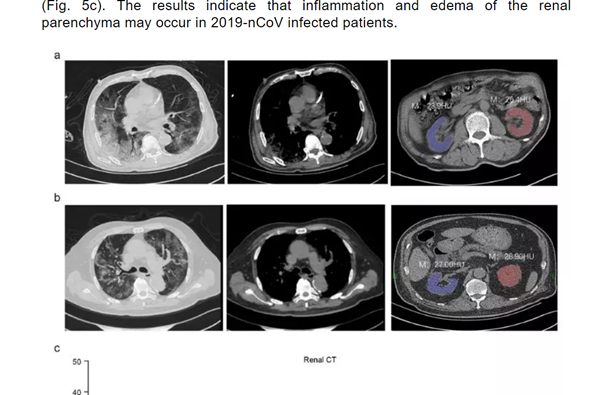

一篇份名为《Caution on Kidney Dysfunctions of 2019-nCoV Patients》的论文,研究了59名来源于武汉、黄石和重庆的59例感染患者病例。

结果发现, 63%的患者表现出肾功能不全的症状,CT扫描显示100%的患者肾脏影像学异常。

(图片来源:Medrxiv)